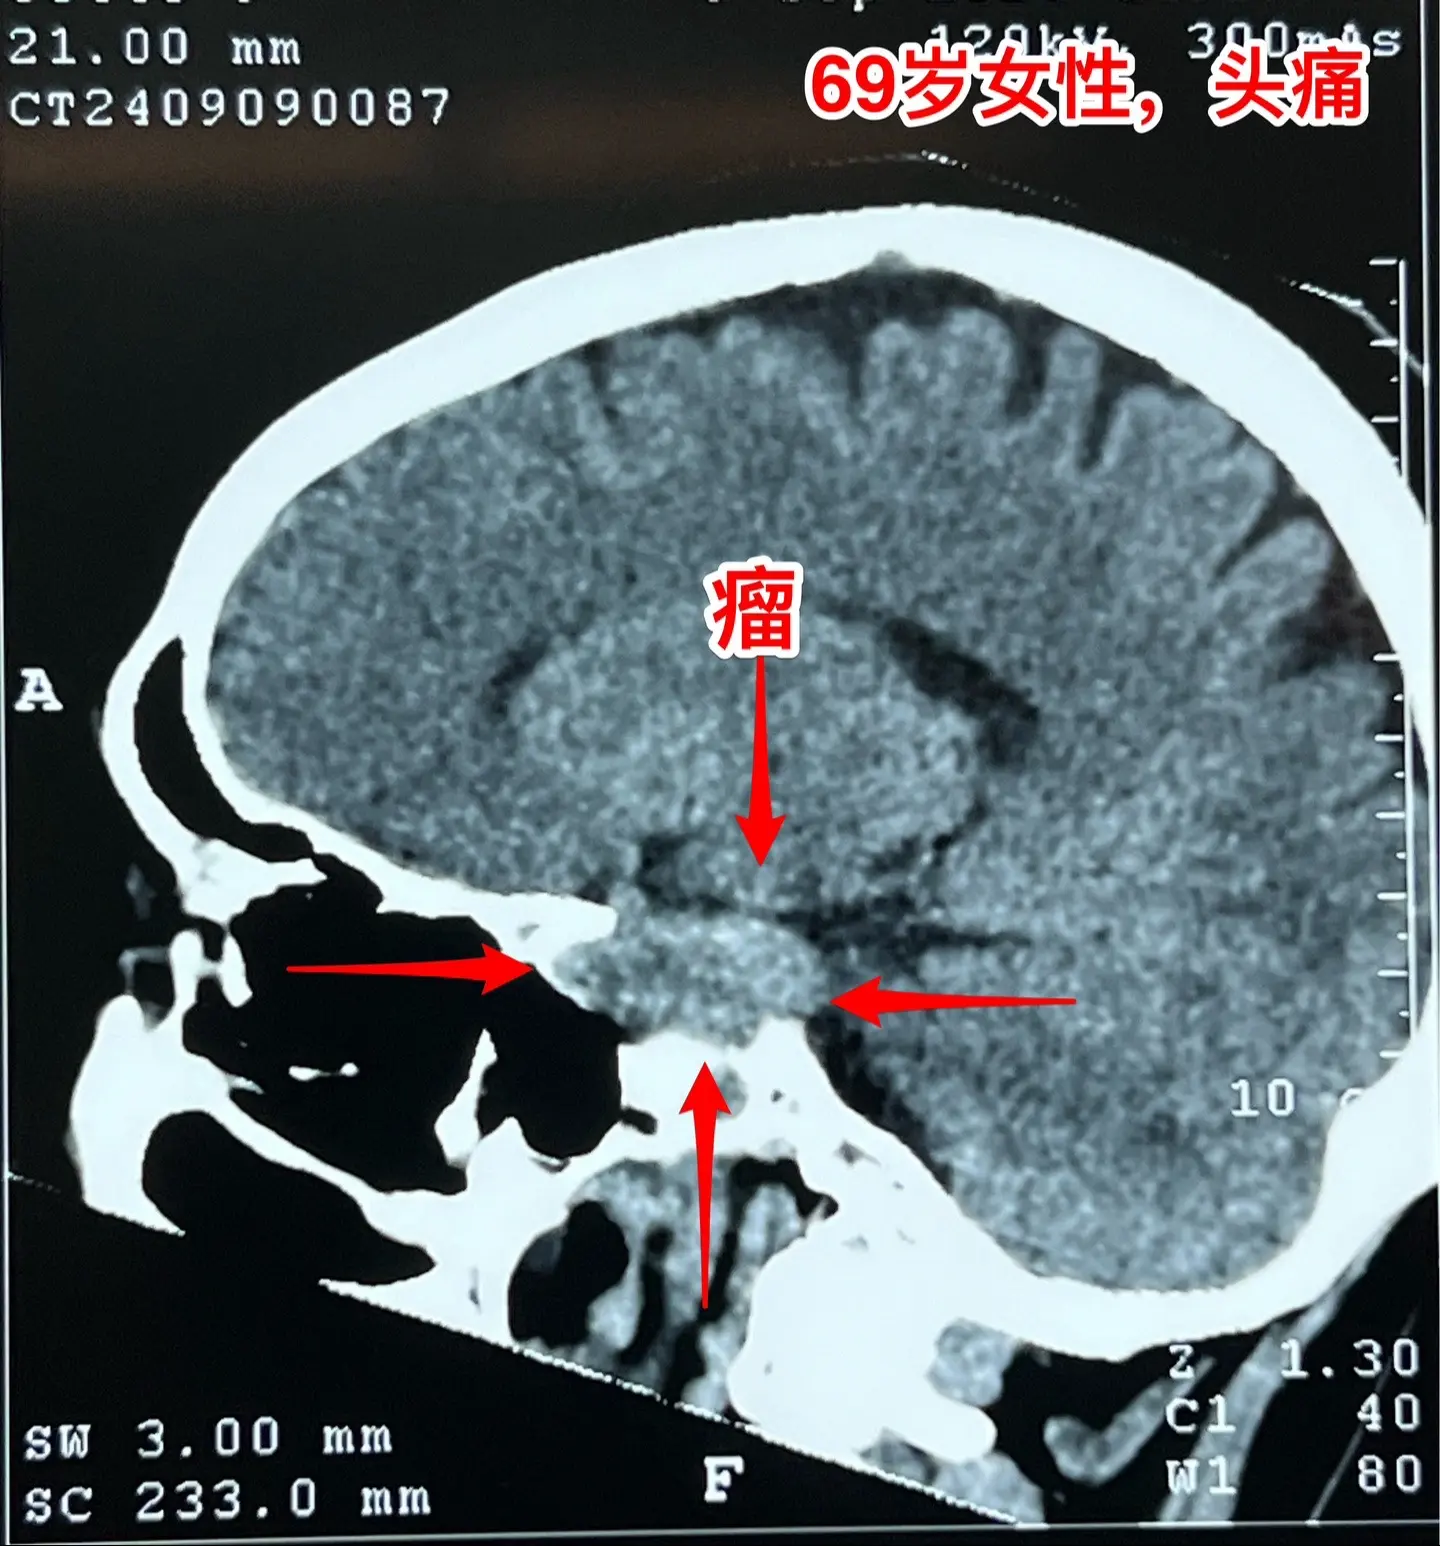

海绵窦区神经鞘瘤,是良性肿瘤。69岁青岛市老太太经常感到头痛,不太剧烈,没有专门去检查。九月份检查脑部磁共振发现左侧海绵窦长了肿瘤。在我院住院后作了强化磁共振,看见左侧海绵窦内有个大肿瘤,见图,考虑是神经鞘瘤,神经鞘瘤是良性肿瘤,如果完全切除了就可以治愈。 老太太有两个女儿,积极要求给她作手术。69岁年龄还是有点大,手术是有风险的! 9月12日下午四点开始进入手术室,手术持续到13日凌晨才结束。手术过程很顺利,肿瘤得到完全切除。今天看见老太太精神比较好,准备下地行走。神经鞘瘤海绵窦